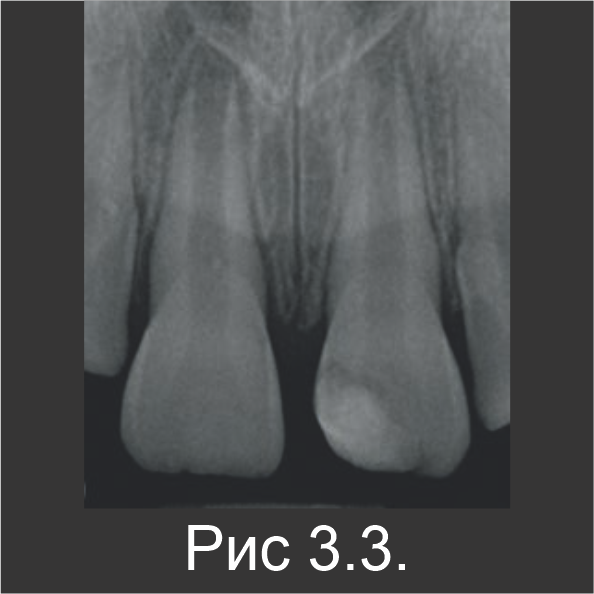

Апексифиция

9-летнюю девочку направили для лечения некроза пульпы незрелого зуба 21, который возник в результате травмы, произошедшей несколькими неделями ранее. В область травмирующего воздействия были вовлечены верхние центральные резцы 11 и 21. Когда материала Biodentine™ еще не было, для апексификации в качестве пробки использовали МТА, а поверх нее нанесли гуттаперчу (рис. 1.1). Через три месяца в зубе 11 также обнаружили некроз пульпы. После стандартного промывания канала гипохлоритом натрия без обработки инструментами, зуб 11 запломбировали гидроксидом кальция и оставили на 1 неделю, чтобы затем выполнить лечение с использованием Biodentine™. В течение второго визита эндодонтический канал запломбировали материалом Biodentine™ по всей длине (рис. 1.2).

Сообщений о постоперационной боли не было. По истечении 6-месячного периода наблюдения патологии на рентгенограмме не наблюдались (рис. 1.3). Клинически в зубе 21, который лечили с использованием МТА, определялось небольшое изменение цвета (рис. 1.4). Известно, что MTA может повлечь изменение цвета коронки, а в данном случае – вероятно, из-за остатков МТА в пришеечной зоне. Патологий в апикальной зоне обоих резцов обнаружено не было.